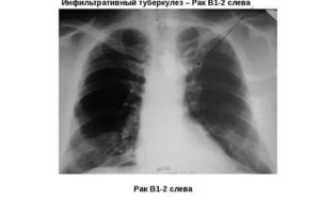

Поэтому важно знать их особенности и в чем разница на снимке между этими недугами.

- Рентген. При поражении микобактериями легкие содержат одну или несколько однородных структур с хорошо просматриваемыми пустотами. При заболевании раком на рентгенограмме наблюдается расширение легочного корня.